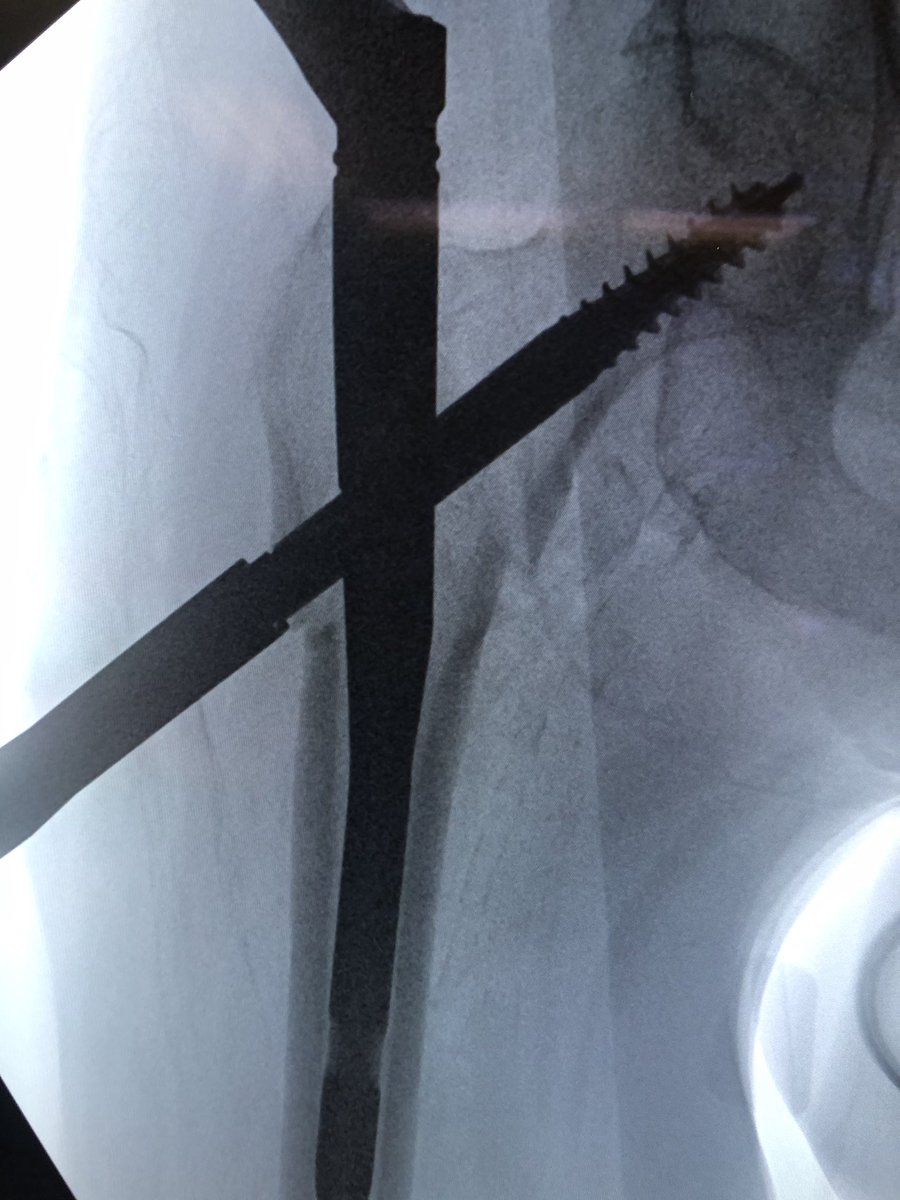

[5/18] Most important: starting point. I draw horizontal line on top of greater troch (green), and hold guidewire up to leg to line up with center of head/neck on perfect lateral & draw line (blue). Stab Incision about 4 finger-breadths proximal / 1 FB anterior to cross of lines.

[6/18] If original start point isn’t good, I leave wire in so new wire doesn’t keep falling into same hole. Also I gently tap to get a foothold instead of using driver so that I can make minute redirections in either plane (yellow). ONLY when I’m happy, I extend stab incision.

[7/18] Once I’m happy with direction, I switch to driver, drive guidewire in metaphysis, then stop and gently tap again. I look for the guidewire to “bounce” off the medial cortex, ensuring it is in bone (not in fracture) and obviating having to go back to the lateral to check.

[9/18] This is where the drawn line comes into play. When you put jig in, you line it up with that line (blue) so that sleeves for the cephalic screw go directly on it. Keep gentle hold on jig (yellow) to keep it from sagging. This way, screw will be close to perfect trajectory.